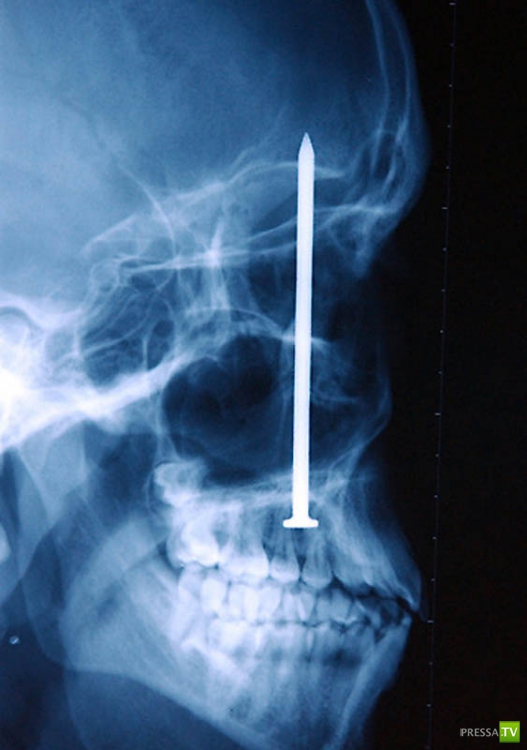

Гвоздь в человеческом черепе – пациент случайно выстрелил в себя из пневматического молотка. Он даже не понял, что выстрелил в себя – 10-сантиметровый гвоздь обнаружили только через 6 дней.